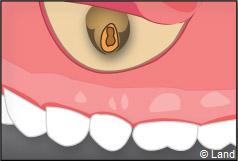

Une anesthésie et une incision semi lunaire sont réalisées et le lambeau de gencive est récliné.

Il faut localiser le bout de la racine de la dent atteinte, procéder au décollement de la lésion avec une curette à bords tranchants, couper et enlever la partie de racine infectée.